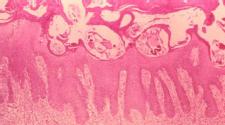

Scabies are a mite-type parasite that burrow under the skin, leading to itchiness and skin eruptions. Typically they're found by looking between the fingers, where they often burrow, but they can spread over the entire body.